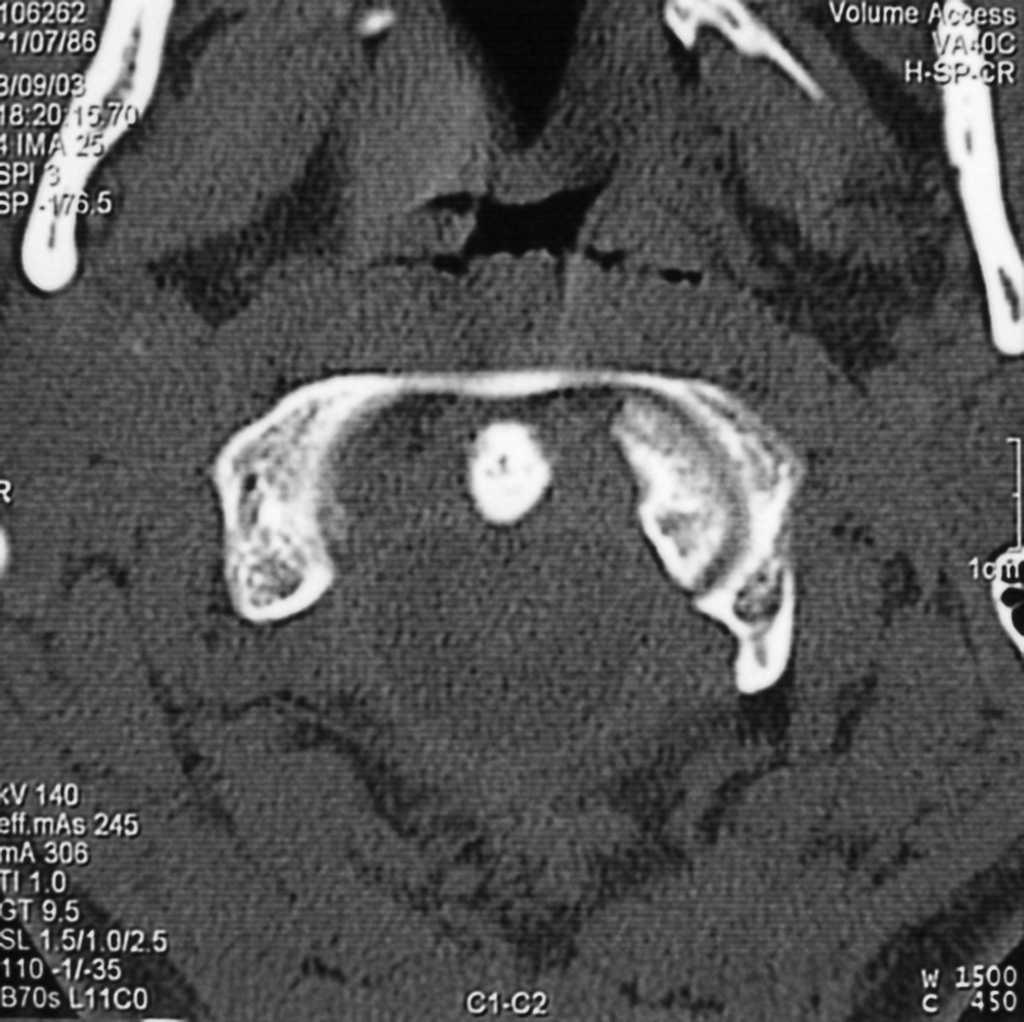

Paciente varón de 9 años con tortícolis asociada a fractura de clavícula por una caída en gimnasia. Tratado en su ciudad de origen mediante vendaje en 8 para la fractura de clavícula, y relajantes musculares y fisioterapia, fue remitido a nuestro centro a las 15 semanas por persistencia de la sintomatología (fig. 1). Las radiografías eran poco demostrativas, por lo que se practicaron estudios mediante TAC y RMN diagnosticándose de SRCAA tipo I3, con una divergencia C1-C2 de 42° (fig. 2); se instauró tracción halo-gravedad progresiva hasta un peso de 7 kg, en que se detuvo por aparición de disartria (17 días de tracción), con una movilidad rotacional levemente disminuida, la TAC de control mostró una divergencia residual de 11°, por lo que para evitar la recidiva se efectuó un artrodesis posterior C1-C2 in situ con injerto de cresta ilíaca (fig. 3), manteniendo la tracción durante la intervención e inmovilizándose con halo-yeso 3 meses. Una vez retirada la tracción, la disartria remitió espontáneamente. Quince años después, el paciente presenta una movilidad cervical prácticamente normal, con una limitación de la rotación izquierda de 10°.

Figura 3. Tomografía axial computarizada posoperatorio del primer paciente, donde se comprueba la buena masa de artrodesis y la divergencia residual de 11°.